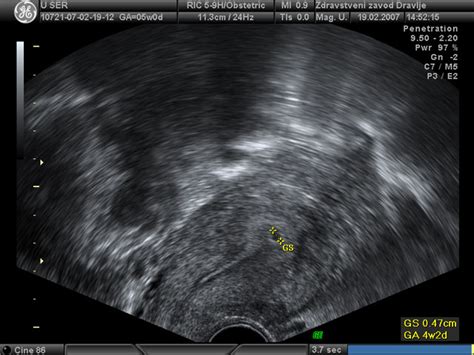

Raven hCG v krvi nosečnice se v prvih tednih nosečnosti hitro zvišuje. Pri ženskah z rednim 28-dnevnim menstrualnim ciklusom, kjer ovulacija običajno nastopi med 13. in 15. dnem, se lahko hCG zazna že med 7. in 10. dnem po spočetju s krvnim testom, medtem ko domači test nosečnosti običajno pokaže pozitiven rezultat med 8. in 14. dnem po vgnezditvi. V prvih tednih se vrednosti hCG običajno podvojijo vsakih 48 do 72 ur. Najvišje vrednosti hCG doseže med 9. in 11. tednom nosečnosti, nato pa postopoma upadajo in se stabilizirajo do konca nosečnosti.

Na primer, pri približno treh tednih nosečnosti (upoštevajoč prvi dan zadnje menstruacije) se vrednosti hCG gibljejo med 5 in 50 mIU/mL, pri štirih tednih pa že presežejo 400 mIU/mL. V sedmem in osmem tednu, ko pogosto poteka prvi ginekološki pregled, se lahko vrednosti gibljejo med 7.650 in 229.000 mIU/mL. Kljub tem smernicam je pomembno poudariti, da se vrednosti hCG lahko zelo razlikujejo med posameznicami in celo med različnimi laboratoriji, zato ena sama vrednost ne more dokončno potrditi gestacijske starosti ali napovedati uspešnosti nosečnosti.